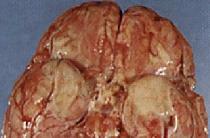

Абсцесс — отграниченное гнойное воспаление, сопровождающееся образованием полости (округлой или сложной формы), заполненной гнойным экссудатом. Он возникает или в уже погибших тканях, в которых нарастают микробно-химические процессы аутолиза (например, при травме), или в жизнеспособных тканях, подвергающихся сильному воздействию микробов (например, при инфекциях) (рис. 31). По периферии это скопление гноя окружено валом грануляционной ткани, через сосуды которой в полость абсцесса поступают лейкоциты (в основном полиморфноядерные) и частично удаляются из нее продукты распада.

Рис. 31 Абсцесс в продолговатом мозге у коровы при листериозе.